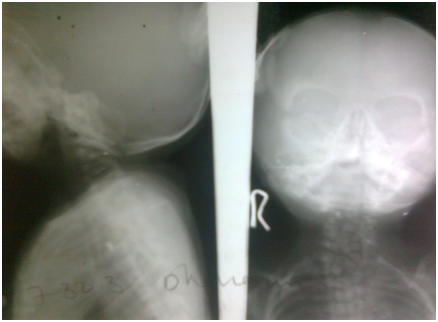

2. X-ray cervical spine AP and Lateral views showed cervical hemivertibrae (Figure 7).

Figure 7 Cervival hemivertebrae.